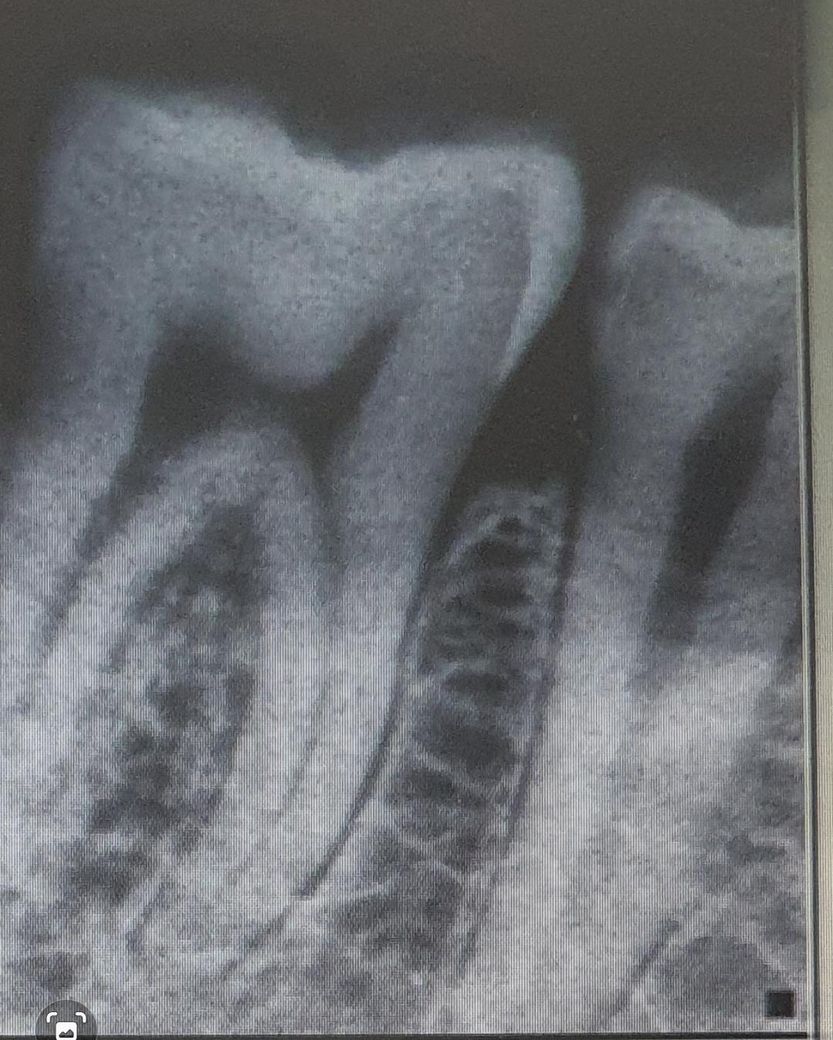

2017년 엑스레이

2025년 엑스레이 입니다.

충치가 안쪽으로 어느 정도 진행된 것으로 보입니다. 인레이 하는 것이 좋을 것으로 판단됩니다.

치료하시는게 좋습니다. 이미 임상사진으로 봐도 거뭇거뭇하게 보이고 방사선사진상으로도 충치가 안쪽까지 진행되어 정지될 우식이 아닙니다.

지금은 신경을 건드리지 않아서 괜찮을 수 있지만 신경이 건드려서 가만히 있어도 아프게된다면 신경치료 및 크라운 치료로 넘어갈 수 있으니 아직 그정도까지 썩지 않았을 때 치료 받으시길 바라겠습니다.

겉으로 보는 것보다는 안쪽 충치가 좀 있을 수도 있습니다. 신경이랑 거리가 얼마 안되는 옆면 충치이므로 미리 치료를 진행해도 좋을 것 같습니다.

오른쪽 아래 J 소구치의 경우에는 인접면에 충치가 있는 것으로 보입니다. 인접면에 충시가 있는 경우 보통 인레이라고 하는 간접 수복 치료를 통해서 치료를 하게 됩니다. 육안으로는 보이지 않지만 인접면에는 충치가 클 수 있기 때문에 치과에서 검사를 하시고 정확하게 치료를 하는 것이 좋을 것으로 생각됩니다.